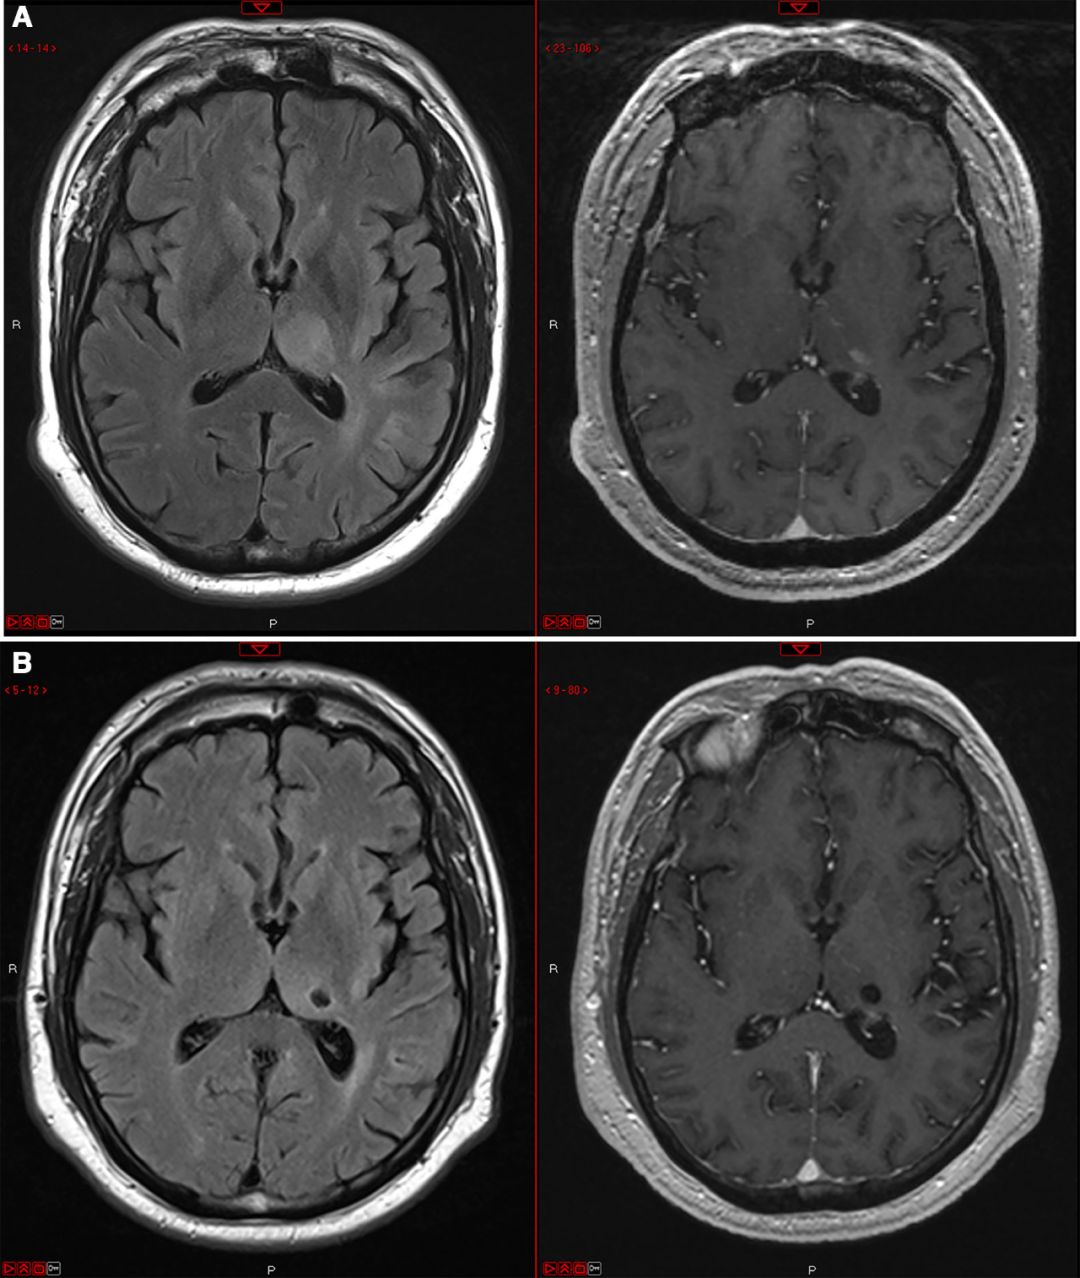

该文展示了一名41岁女性海绵窦血栓引流术后继发感染性动脉瘤的病例,并首次采用了pipeline支架治疗并随访显示治愈(如图所示)。并通过文献检索发现6例海绵窦感染性动脉瘤采用支架治疗成功的病例,文章认为,相比闭塞血管而言,流量导向支架是一个安全有效的选项。